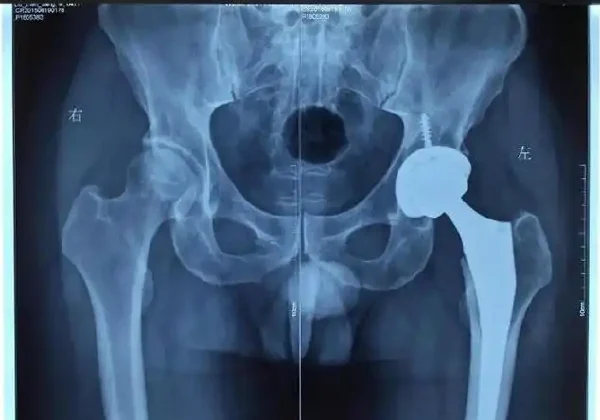

尽管体格检查有助于初步筛查,但确诊股骨头缺血性坏死依赖于影像学检查。X线检查可以发现骨结构的异常变化,这是早期诊断的重要工具。MRI被认为是诊断股骨头缺血性坏死的“金标准”,能够在早期阶段发现病变,并评估病变范围和严重程度。

根据影像检查结果,医生会进行综合分析。通过这些方式对患者的症状和风险因素进行评估,从而得出初步诊断。结合辅助检查(如实验室检查、骨扫描),最终确诊股骨头缺血性坏死并提出后续治疗方案。